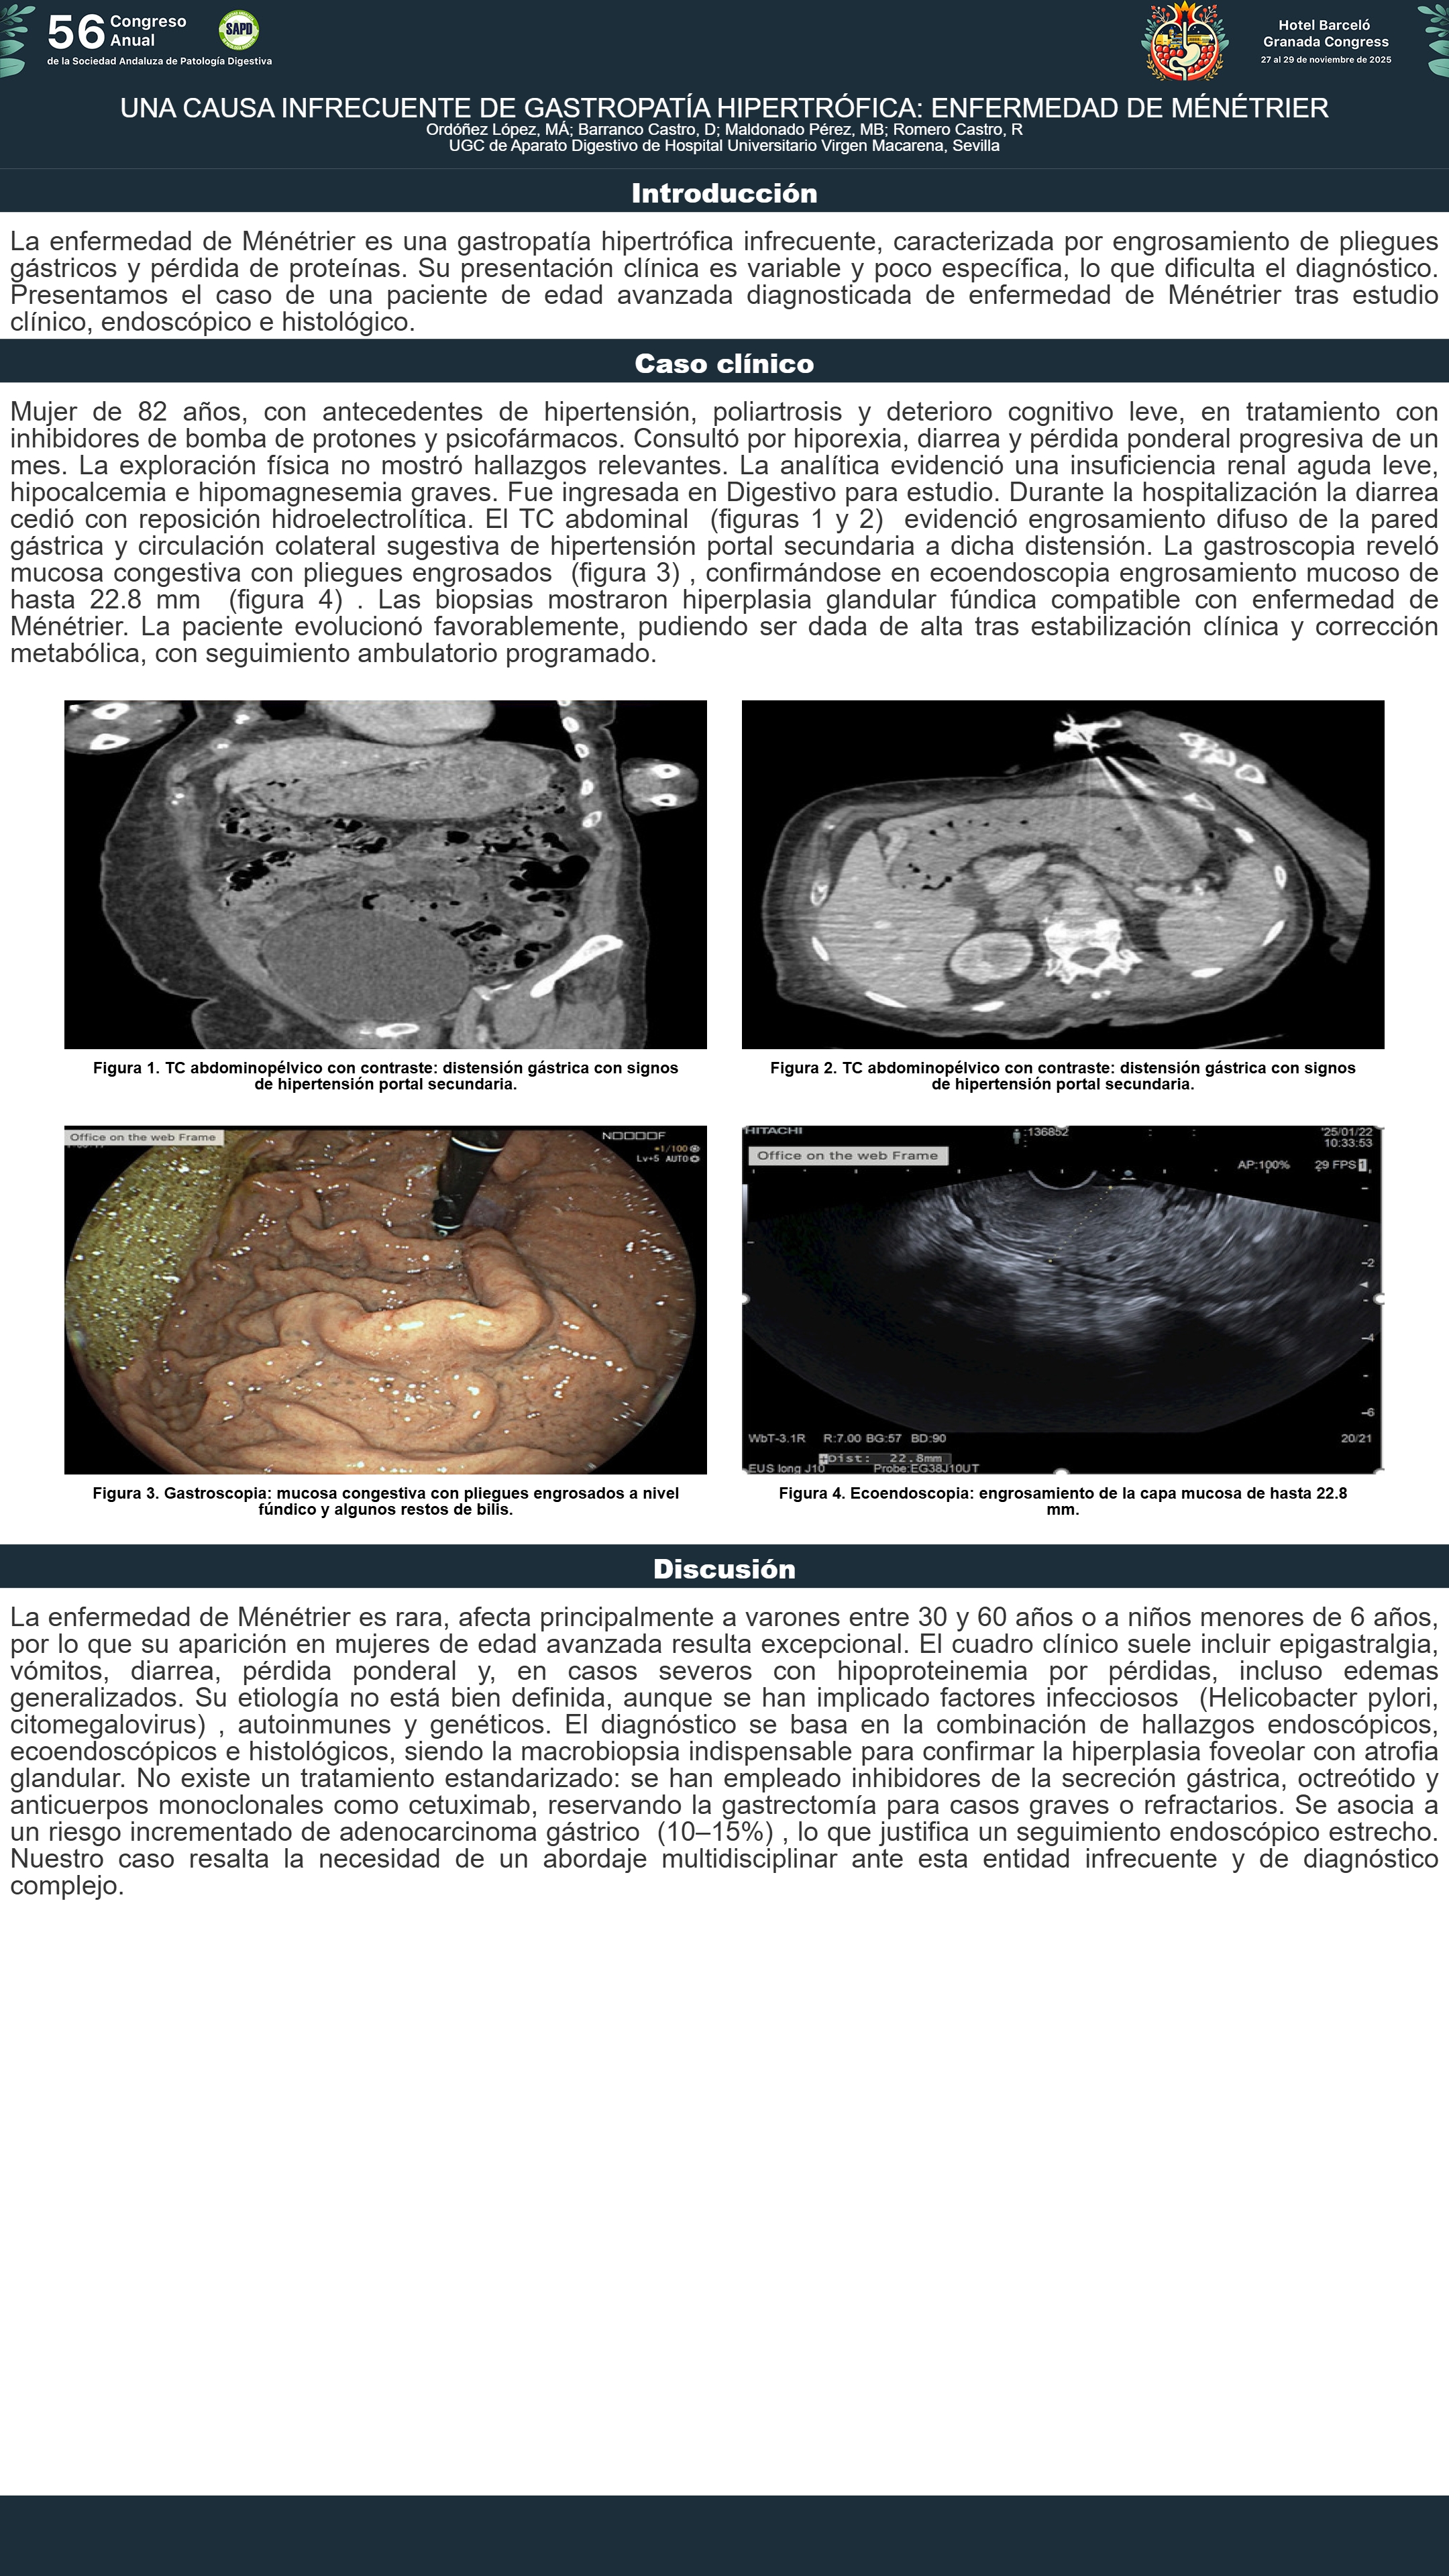

[CP-024] UNA CAUSA INFRECUENTE DE GASTROPATÍA HIPERTRÓFICA: ENFERMEDAD DE MÉNÉTRIER